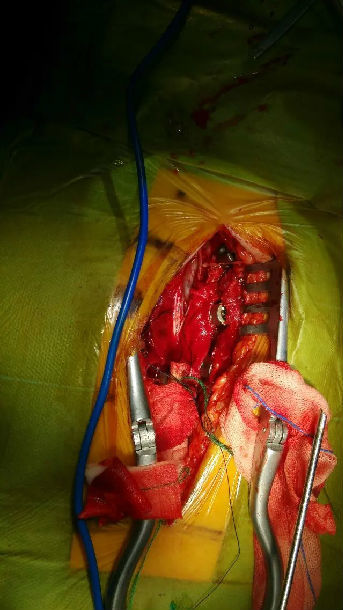

手术经过及所见如下图: